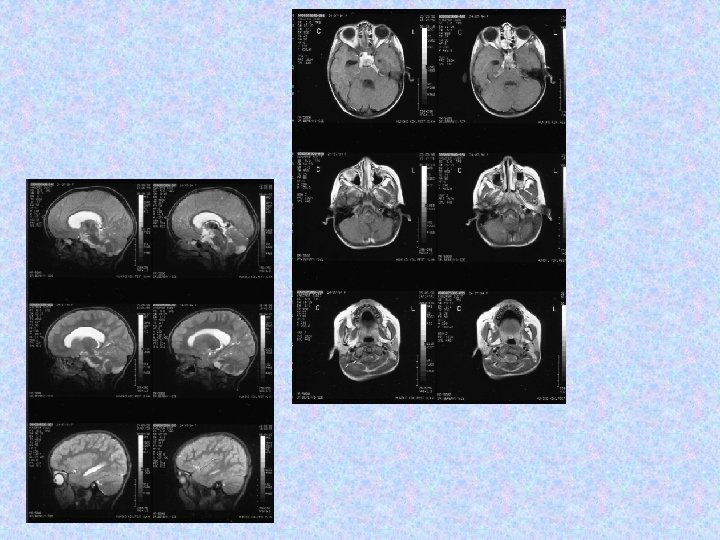

• 1998. december 10 -én arachnoideális biopszia történt szuboccipitális kraniotómiából, ami meningeális gliomatózist igazolt alacsony proliferációs indexszel. Szövettanilag pilocitás asztrocitóma igazolódott. Komplikáció, neurológiai novum nem lépett fel. A disszemináció miatt sugárterápia javasoltak az egész koponyára és gerincre. • A gyermek kemoterápiában részesült 1999. februárjában és márciusában, a sugárterápiát 1999. júniusában és júliusában kapta. • A 2000. április 10 -i MR változatlan craniális és spinális állapotot mutat. Neurológiai novum nem alakult ki.

• 2000. december 4. !!! MRI majdnem teljes intracerebrális és teljes spinális regressziót mutat. !!!

• 2002. július 10 -én koponya és teljes gerinc MRI felvétel történt. A koponya MRI felvételek összevetve a 2001. június 27 -i felvételekkel aszimmetrikus kamrarendszert mutattak, a bal kamra kitágulásával. A jobb kamra szűk, a shunt vége a frontális szarv dorzális részében helyezkedik el, jól működik. A harmadik kamra területén egy intenzíven halmozó terime látható, továbbá bal kamraszarvban bazálisan. A szubarachnoideális liquorterek megtartottak, kóros halmozás nem figyelhető meg. • A gerinc MR felvételen a kraniocervikális átmenetben, a nyúltvelő ventrális felszínén sáv alakú halmozást írtak le. Th. VII-VIII. , L. I-II. csigolyákban, a conus körül szolid halmozás figyelhető meg. Az alacsonyabb thoracalis szakaszokon lévő myelon felszínén és intradurálisan homogén halmozást írtak le. • A neuro-onkológiai konzílium nem javasolt további kemo- és radioterápiát.